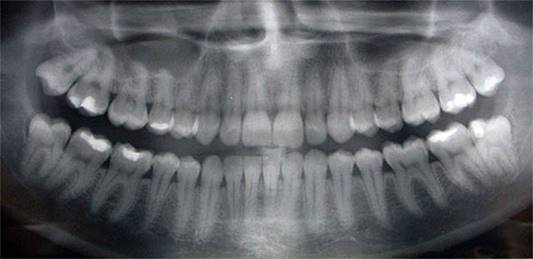

One of the key tools we use in Dental Decoding in addition to the clinical examination of the patient is the study of panoramic radiography (panoramic x-ray). We can use it to analyze several factors that are not seen with the naked eye including the shape and position of the roots of the teeth.

dientes.jpg

Using this technique, we can discover in the family tree what we need to heal. Dental Decoding offers the ability for us to heal our lives and the pain of our ancestors that has marked the direction of our unconscious destiny. Together with Psychogenealogy we can find our Happy Destiny!